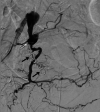

Arterioureteral fistula (AUF) is a direct communication between the ureter and an artery and is a rare cause of catastrophic, life-threatening haematuria. Fistulation may occur between the ureter and the abdominal aorta, common iliac, external and internal iliac, and inferior mesenteric arteries, and is typically observed in patients with a prior history of pelvic radiotherapy, oncological pelvic surgeries, aortoiliac vascular procedures, and pelvic exenteration. There is also an increased frequency of cases amongst patients who have undergone urological diversion surgeries and in those with chronic indwelling ureteric stents requiring repeated exchange. As AUF is so rarely encountered in clinical practice, the urologist may fail to appreciate its presence until late in the patient's presentation; such diagnostic delay is associated with high mortality and thus rapid clinical suspicion and investigative action are necessary. There are sporadic cases of this rare entity mentioned in literature. In this report, we present two cases as well as a review of the literature. A 73-year-old female presented with repeated episodic haematuria for a week in whom the cause of symptoms remained persistently elusive despite repeated imaging and operative approaches. An eventual diagnosis of a secondary right internal iliac-ureteral fistula was ascertained on a subsequent digital subtraction angiography of the renal tract. The fistula was embolised using an endovascular approach. The patient remained stable post emobilisation and was successfully discharged shortly after the procedure. In the second case, a 51-year-old female, presented with hematuria from her ileal conduit for a few days. Initially, the cause of symptoms was thought to be due to ureteric stents. During a change in her stents, brisk bleeding led to further investigation including an iliac angiogram confirming bleeding from the left common iliac artery. She had a covered common iliac artery stent, which successfully controlled her bleeding This report emphasizes the diagnostic difficulty of AUF, outlines the management principles of this rare disease, and aims to increase awareness of this rare yet potentially lethal phenomenon among practitioners of urology and interventional radiology.